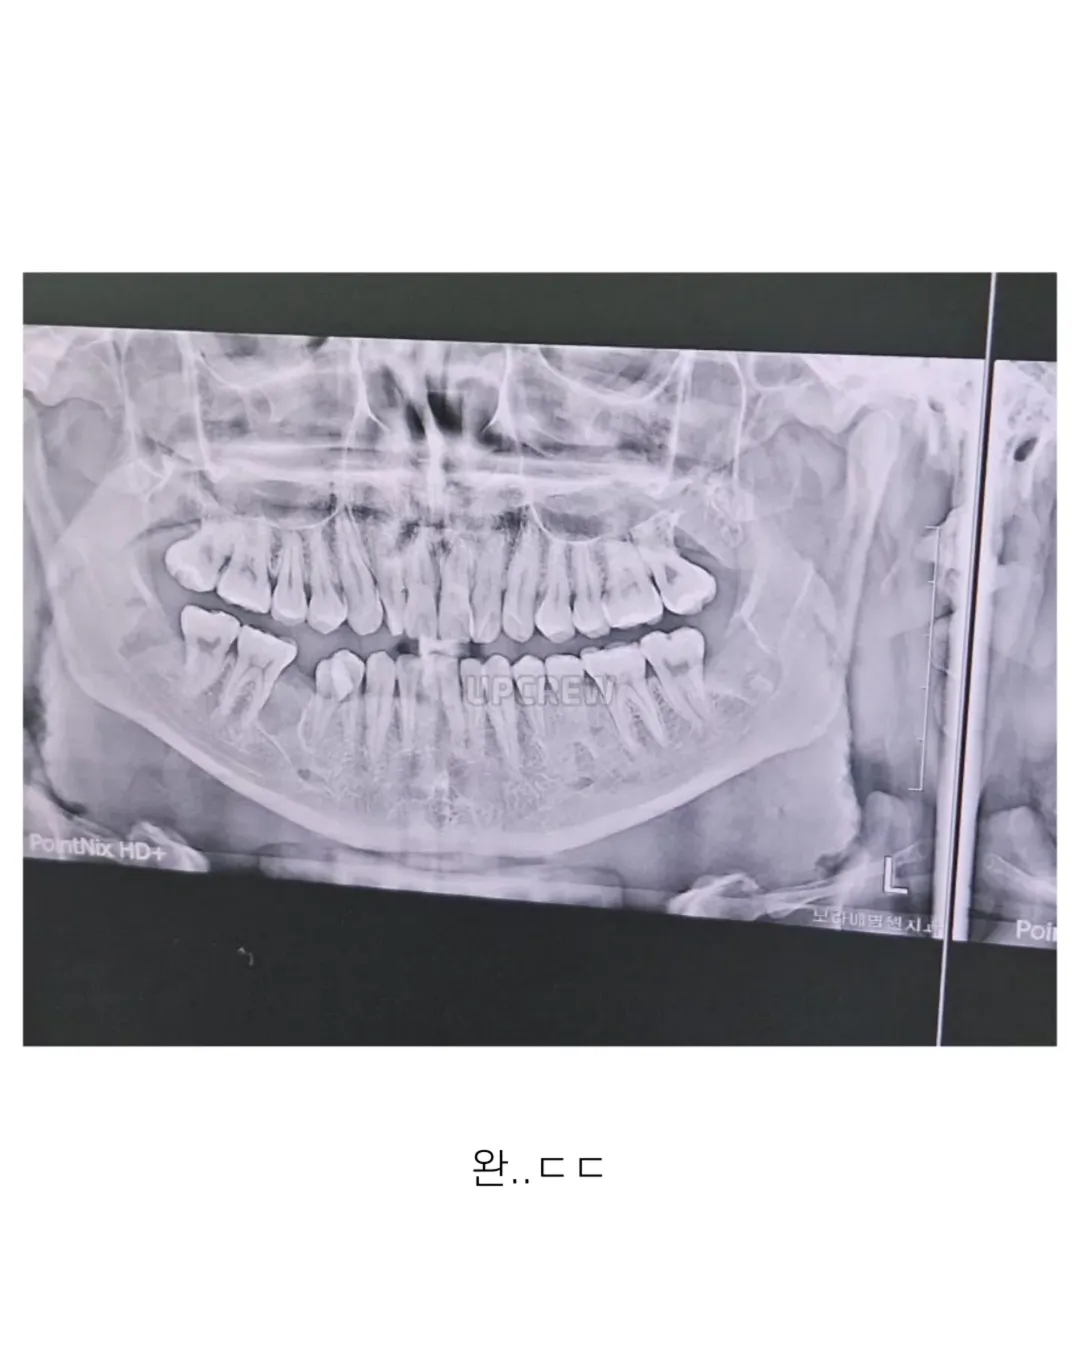

사랑니 갤러리의 특이한 사랑니들 (약혐 주의)

하.. 나는 애매한데 사랑니가 코 근처에서 둥둥 떠있음..ㅠ 왜 이렇게 된건지는 모르겠는데 치과의사쌤이 얼굴뼈 안쪽에 물이차서 사랑니가 같이 올라가버려서 뭐 어떻게 할수가 없다고 함..ㅜ 불편한거 없으면 괜찮을 것 같은데 나중에 빼고싶으면 위험 감수하고 대학병원가서 주사로 입천장 뚫어서 물 다 빼내고 사랑니가 밑으로 내려오길 기도하고 내려오면 수술해야한다고 하더라 레전드

코랑니ㅋㅋㅋㅋㅋㅠ

코랑닠ㅋㅋㅋㅋㅋㅋ